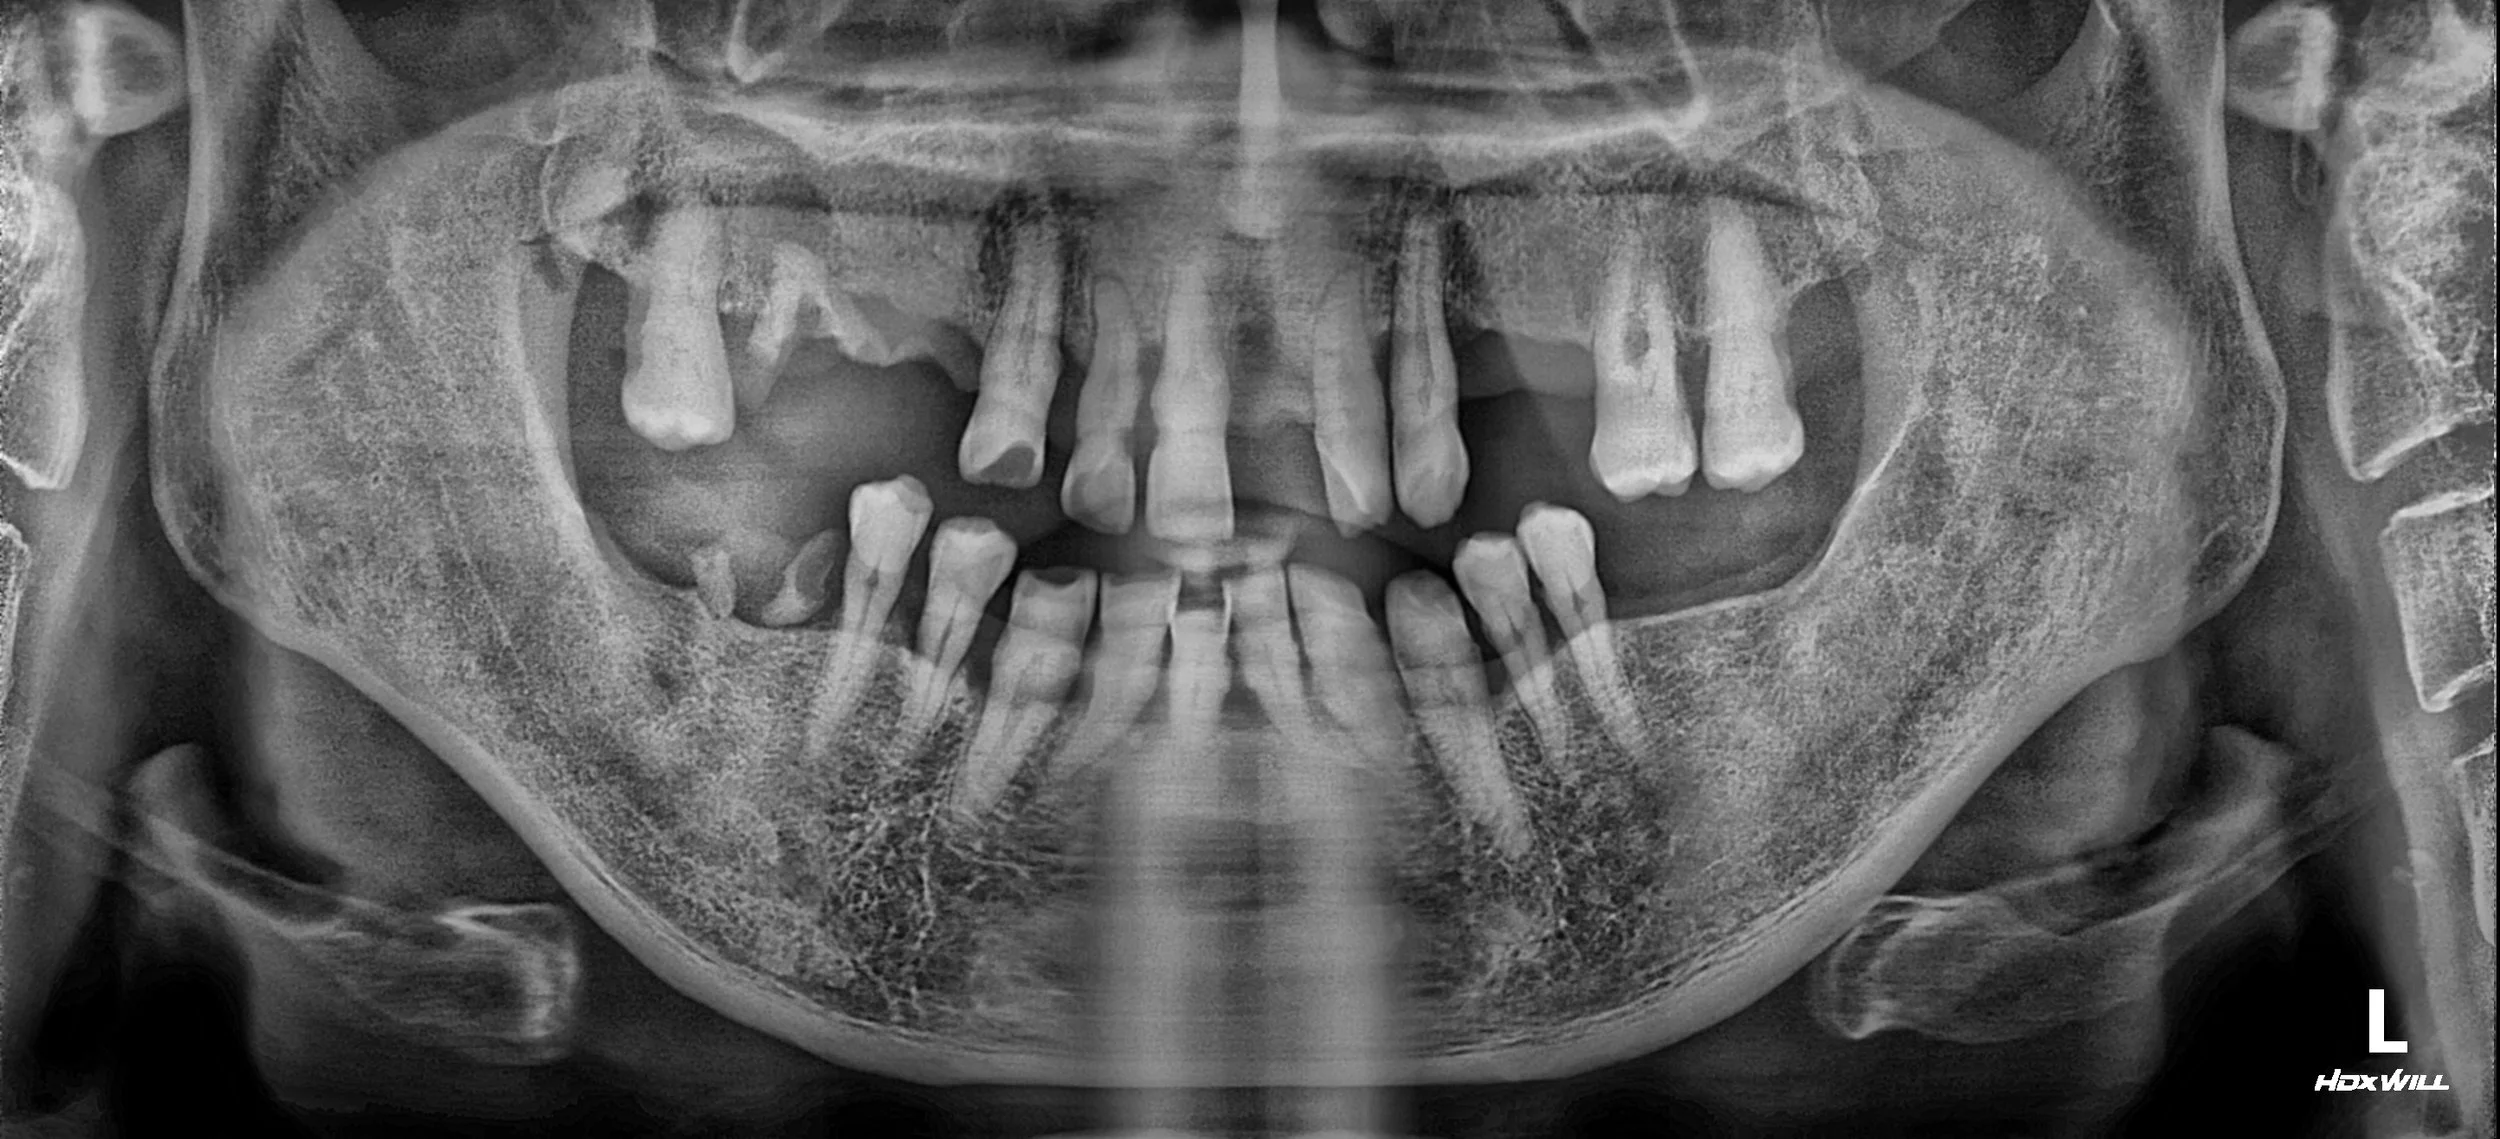

OPG - BEFORE

A male patient in his 50s presented with a severely compromised dentition. Years of progressive periodontal disease had led to:

• Generalized Tooth Loss: Multiple missing units in both the maxillary and mandibular arches.

• Loss of Occlusal Relationship: The lack of posterior support had caused a total breakdown of the bite, making mastication nearly impossible.

• Periodontal Instability: Severe horizontal bone loss and increased tooth mobility were evident across the remaining dentition.